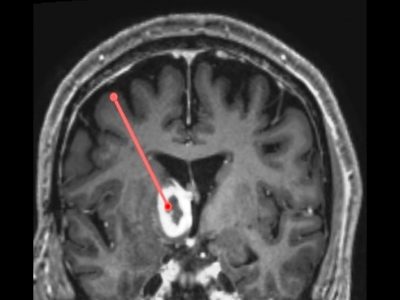

Welcome to this e-learning resource for stereotactic functional neurosurgery and DBS, with focus on visual anatomical targeting.

The aim of this website is to cover every detail of DBS that is of importance from a clinical perspective, including the most fundamental basics. The site is therefore suitable for young colleagues who are starting their training within the field of stereotactic functional neurosurgery and DBS. Hopefully, some of the lectures will also be of value to more experienced colleagues, and to nonneurosurgeons with an interest in DBS.